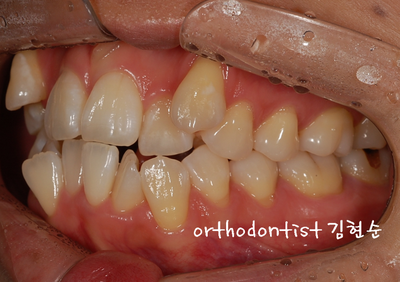

교정 문의 환자는 29세 직장 여성분으로 송곳니 돌출로 문의해 주셨습니다

예상 교정 기간 약 18 ~ 20 개월

- 환자분은 웃을 때 크게 웃지 못하는 스트레스로 고통을 받았습니다

치아 배열이 안 좋고 이상하며, 공간 부족으로 인한 덧니 와, 아래턱 돌출 경향으로 보여집니다,

사랑니 매복과 함께, 충치 치료 요함

- 치아 배열 개선을 위한 발치 교정으로 위의 하늘색 X 표 치아를 발치하였습니다. ( #14, 24, 34, 44, ext )

발치 공간으로 치아를 배열 후 정상 교합으로 되도록 조절하였습니다

상악 mini - screw 식립을 하였습니다

- 교정 전후 의 모습이 많이 달라 보입니다 이 모습 오랫동안 간직하세요 ~~^^